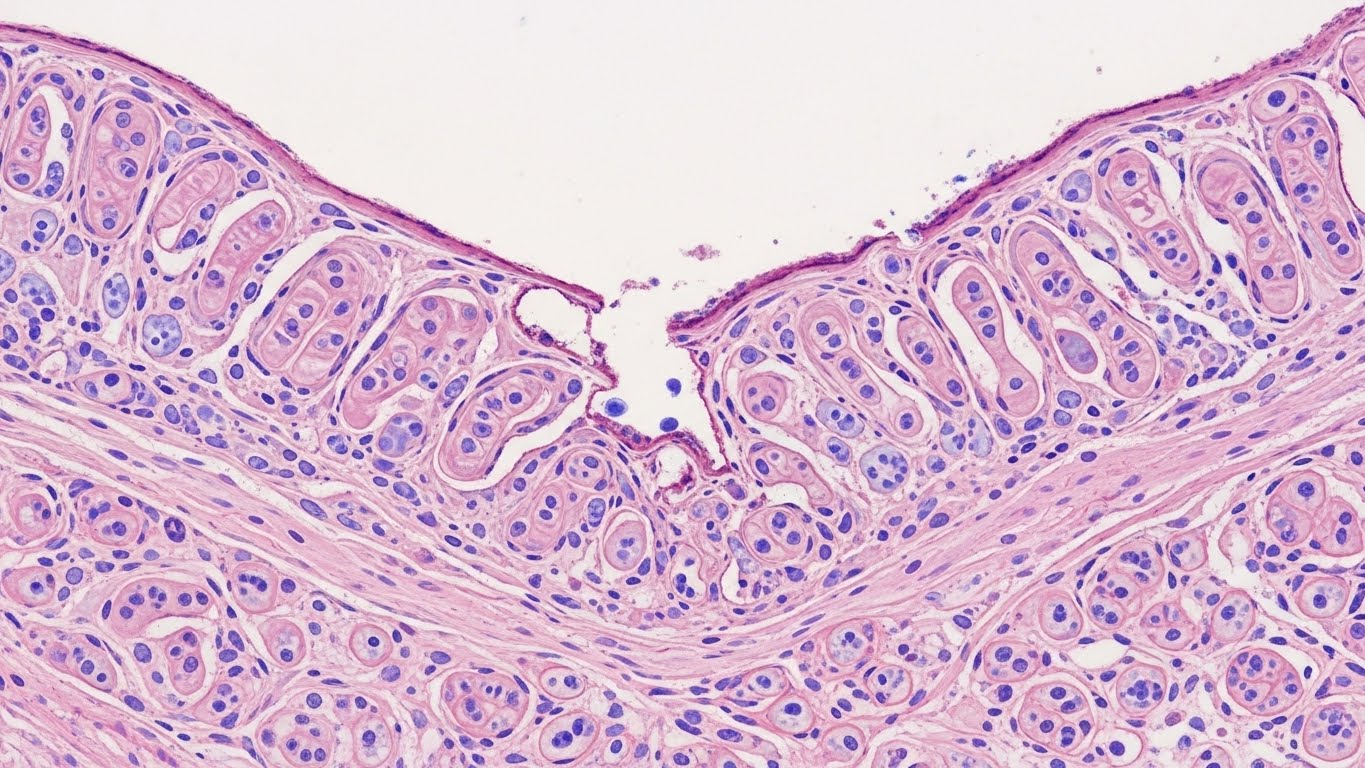

크론병은 입에서 항문까지 소화기관 어디든 염증이 생길 수 있는 만성 염증성 장 질환입니다. 초기에는 단순 장염이나 과민성 대장 증후군으로 오해하기 쉬워 주의가 필요합니다.

A. 크론병은 조직검사와 내시경을 통해서만 정확한 진단이 가능하므로 필수입니다.